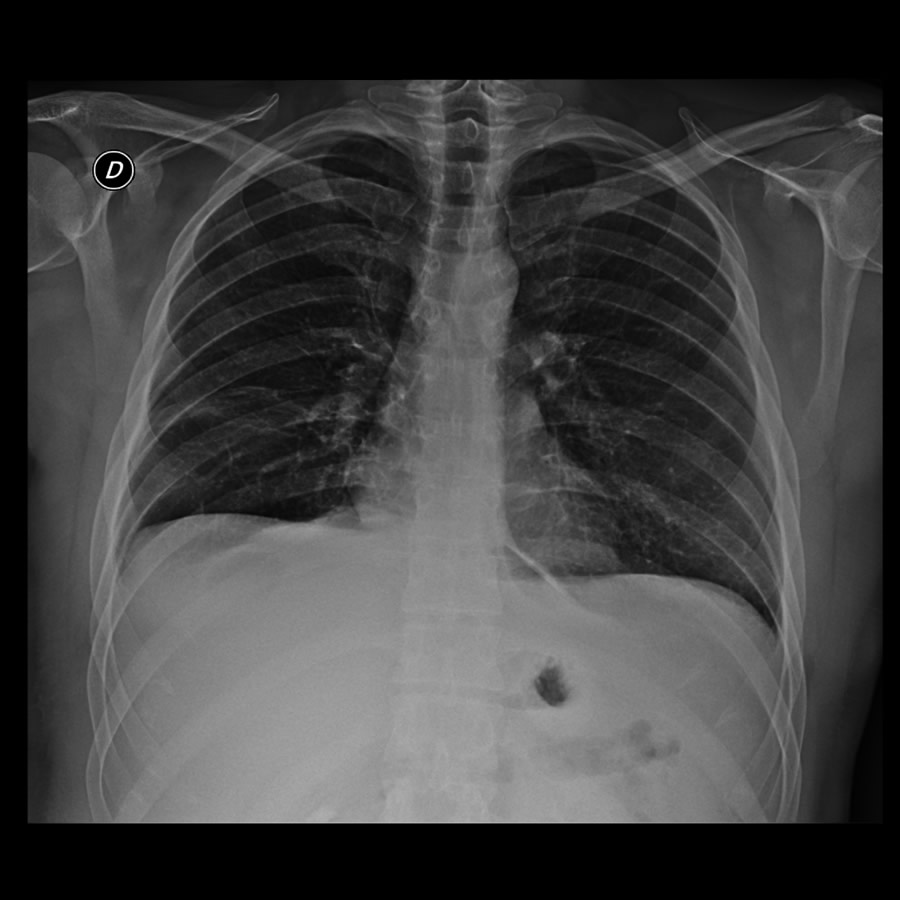

Paciente masculino de 34 años con distensión y dolor abdominal.